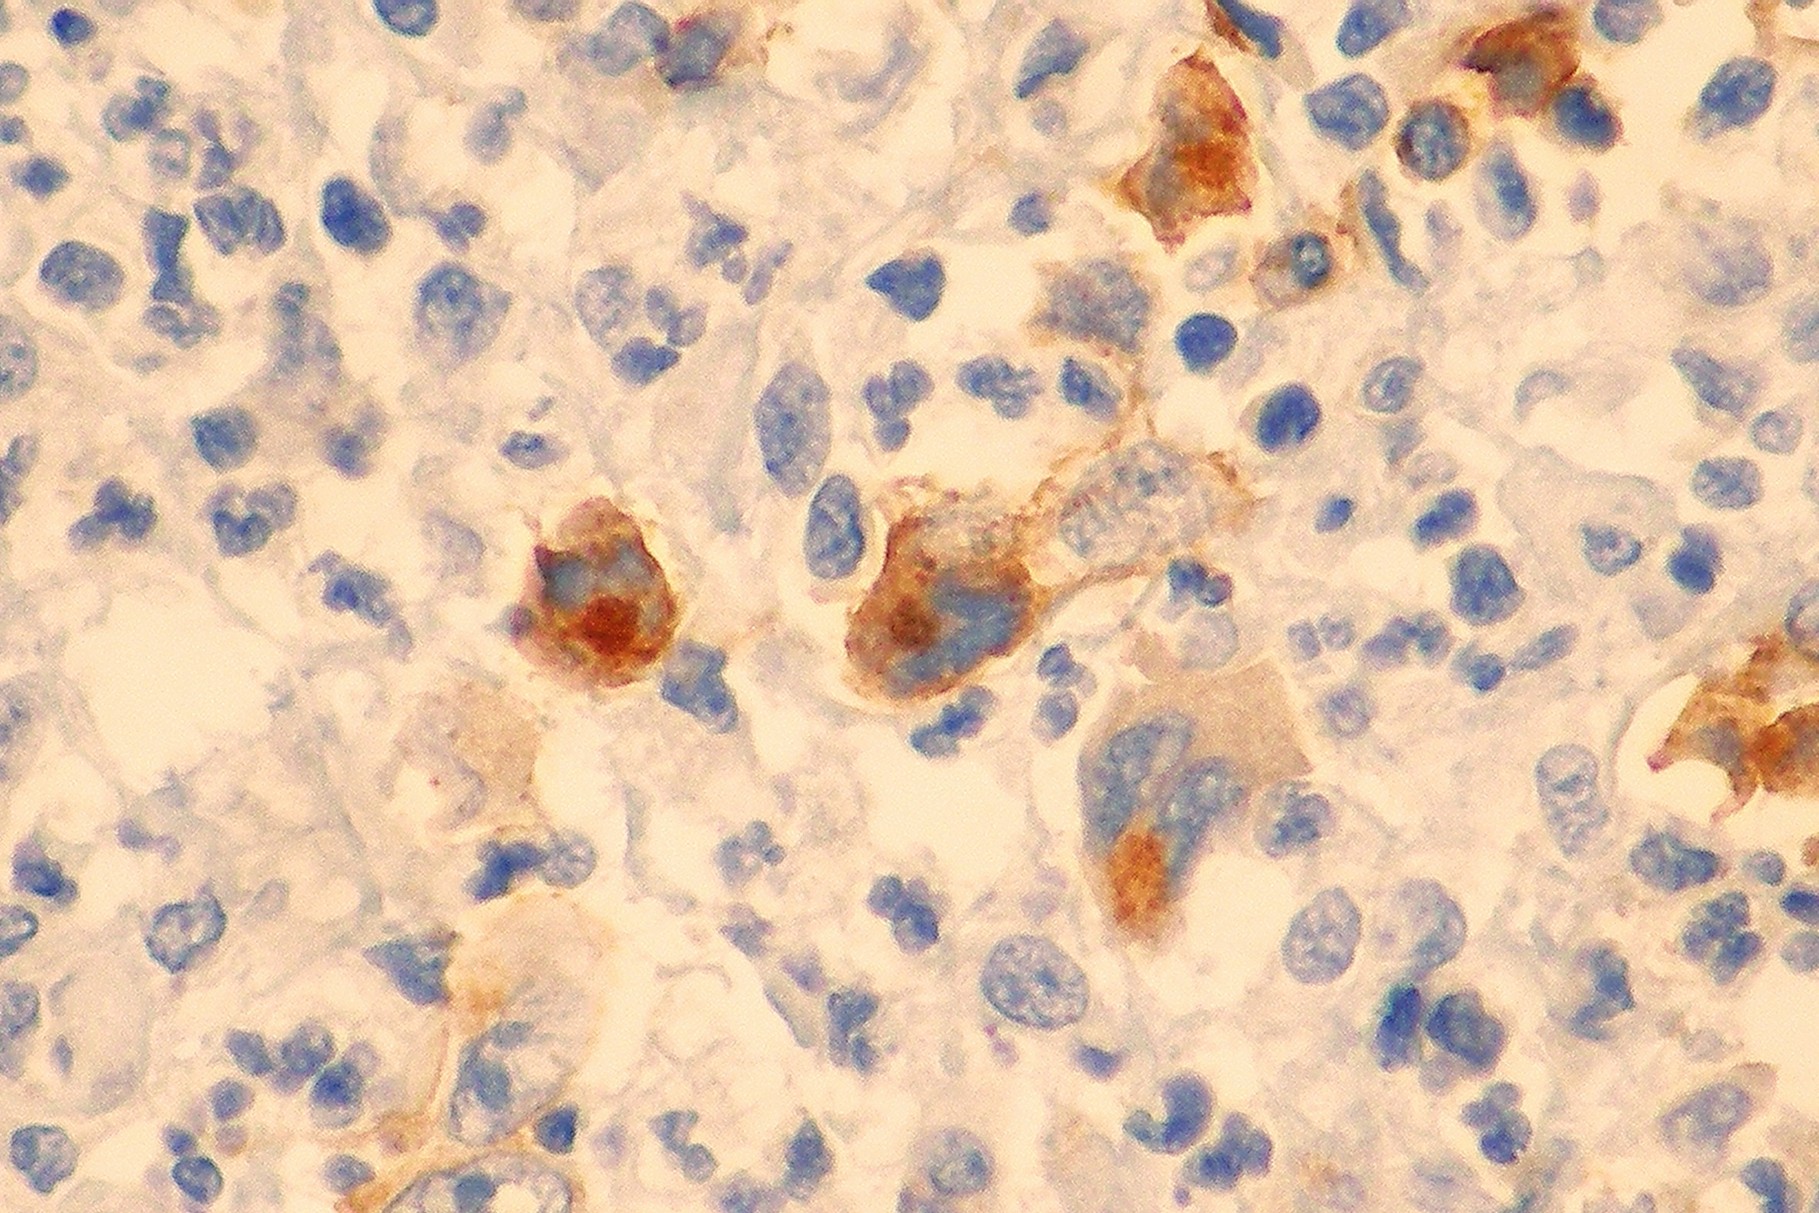

Patología Molecular

El diagnóstico sobre muestras de tejidos y líquidos corporales en plena era de la medicina del futuro, está basado en la integración de técnicas y conocimientos diferentes.

Hoy más que nunca es importante integrar una buena historia clínica con un correcto estudio de imagen y una buena morfología que además puede estar apoyada con proceso especiales complementarios relacionados con la Inmunología, Biología Molecular y Citogenética, generando así un estudio integral conocido como Patología Molecular.